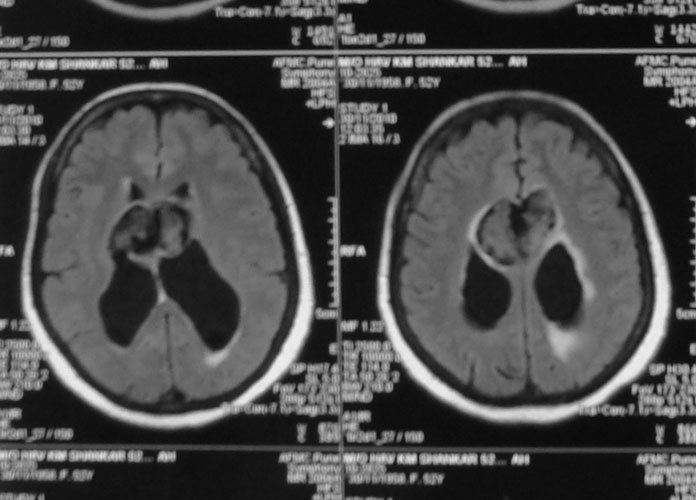

Hydrocephalus

Hydrocephalus is a common problem in the childhood, due to obstruction to the flow of cerebrospinal fluid (‘clear fluid within the brain cavities’). Child presents with an enlarging head, headache, vomiting, drop in school performance. MRI is required to diagnose hydrocephalus, and to ensure that there is no brain tumor causing obstruction. Treatment is insertion of ventriculoperitoneal shunt from brain to the abdomen. In older children, endoscopic third ventriculostomy too can be considered.

Medulloblastomas

Medulloblastomas are common tumors in childhood, often presenting with vomiting and headache. These tumors are located in midline of the cerebellum (back of the head). Diagnosis is made with MRI, and complete excision can be done safely in majority of the children.